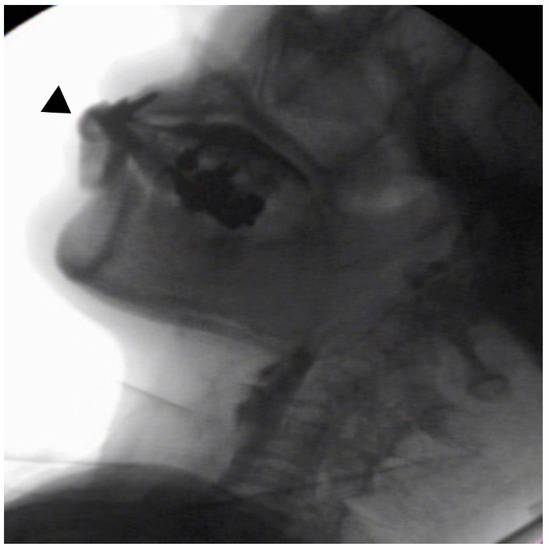

In the seated position, spoon-feeding was infeasible and bolus transport did not occur; furthermore, anterior–posterior tongue movement caused most of the food to dribble out of her mouth. After placing food on top of her tongue using a tube-fitted syringe, most still dribbled out of her mouth (Figure 1a); however, a proportion was transported into the pharynx (Figure 1b). Furthermore, after placing food at the back of her tongue with the patient reclined at 30°, a small amount still dribbled out of her mouth; however, the patient could swallow without aspiration (Figure 2). After increasing the amount placed in her mouth at one time to 7 mL, more food dribbled out of her mouth (Figure 3); additionally, there was a decreased amount transported to the pharynx. When 5 mL of a moderately thick paste was placed in her mouth, none of it dribbled out; however, slight silent aspiration was present (Figure 4). There were no particular issues observed due to peristalsis from the upper esophagus to the stomach.

Figure 4.

The patient was reclined at 30° for the administration of 5 mL of a moderately thick paste. There was delayed triggering of the swallowing reflex; moreover, silent aspiration occurred (▲).